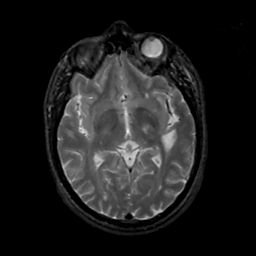

MR Study #14, June 2, 1991 -- Slice #24